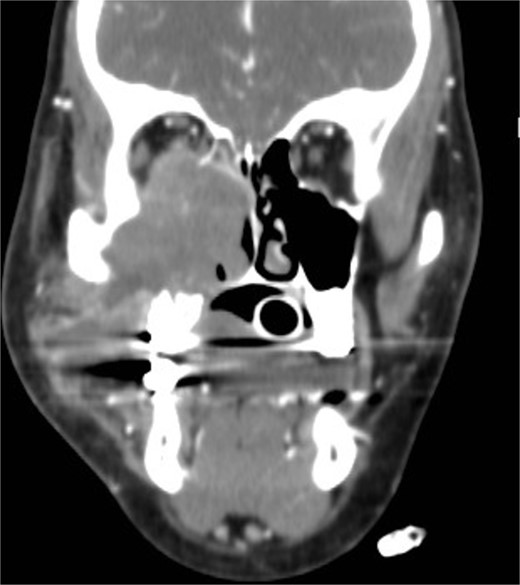

Isolated maxillary fungal ball

A 30-year-old lady presented to the clinic with a complaint of right facial pain, recurrent rhinorrhea with post-nasal discharge, nasal endoscopic examination was unremarkable. A non-contrast computed-tomography scan (NCCT) of the paranasal sinuses (Fig. 1) was suggestive of isolated right fungal maxillary fungal ball (FB). The patient underwent endoscopic sinus surgery (ESS) with (Fig. 2) right middle meatal antrostomy and removal of fungal debris. The patient was followed up regularly and remained symptom free.

Axial (A) and coronal (B) images of a nonenhanced CT scan of the paranasal sinuses showing right maxillary sinus complete heterogenous opacification.